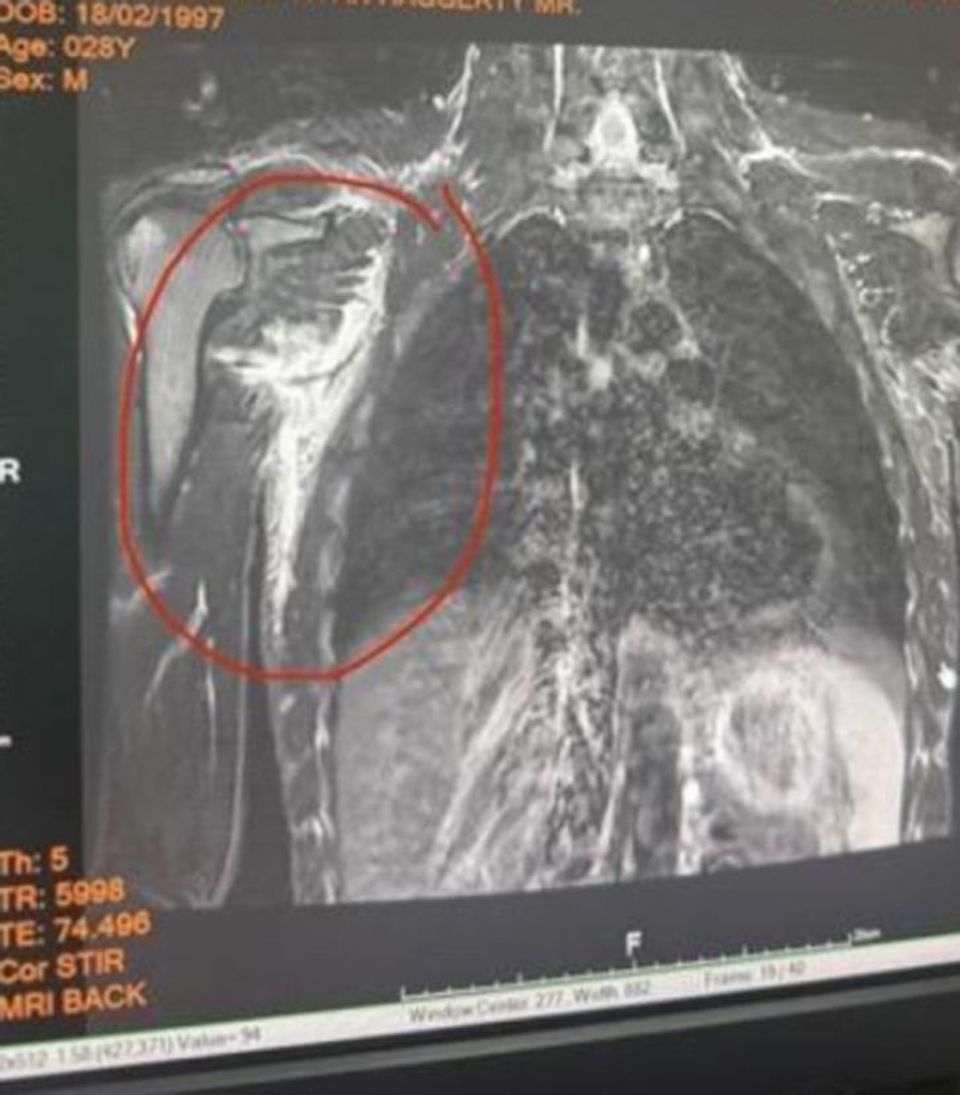

โจนาธาน แฮ็กเกอร์ตี” แชมป์โลก ONE คิกบ็อกซิ่ง รุ่นแบนตัมเวต (135-145 ป.) วัย 28 ปี จากอังกฤษ ออกมาเปิดใจถึงอาการบาดเจ็บล่าสุด ซึ่งส่งผลให้เจ้าตัวต้องถอนตัวในไฟต์ชิงบัลลังก์ ONE มวยไทย รุ่นแบนตัมเวต กับ “นาบิล อานาน” นักชกก้านยาวสัญชาติไทย-แอลจีเรีย ในศึกใหญ่ ONE 173 ที่จะจัดขึ้นในวันอาทิตย์ที่ 16 พ.ย. 68 ณ สนาม อาริอาเกะ อารีนา กรุงโตเกียว ประเทศญี่ปุ่น

“แต่โชคร้าย เมื่อ 3 สัปดาห์ก่อน ผมได้รับบาดเจ็บที่มือซ้าย ต้องเย็บถึง 8 เข็ม ตอนนั้นผมคิดว่าเป็นแค่เรื่องเล็ก ๆ ที่จะผ่านไปได้ จึงตัดสินใจซ้อมต่อ ทีมงานช่วยผลักดันผมอย่างเต็มที่เพื่อให้ฟิตทันขึ้นชก แต่สัปดาห์ถัดมา ผมเกิดบาดเจ็บซ้ำ เอ็นหัวไหล่ฉีกจนลามไปถึงกล้ามเนื้อหลัง ซึ่งเกิดขึ้นระหว่างซ้อม ตอนออกหมัดแรกผมก็รู้แล้วว่ามันผิดปกติ จึงรีบไปตรวจด้วยคลื่นแม่เหล็กไฟฟ้า (MRI) และผลก็ยืนยันว่า ผมไม่สามารถขึ้นชกไฟต์นี้ได้”